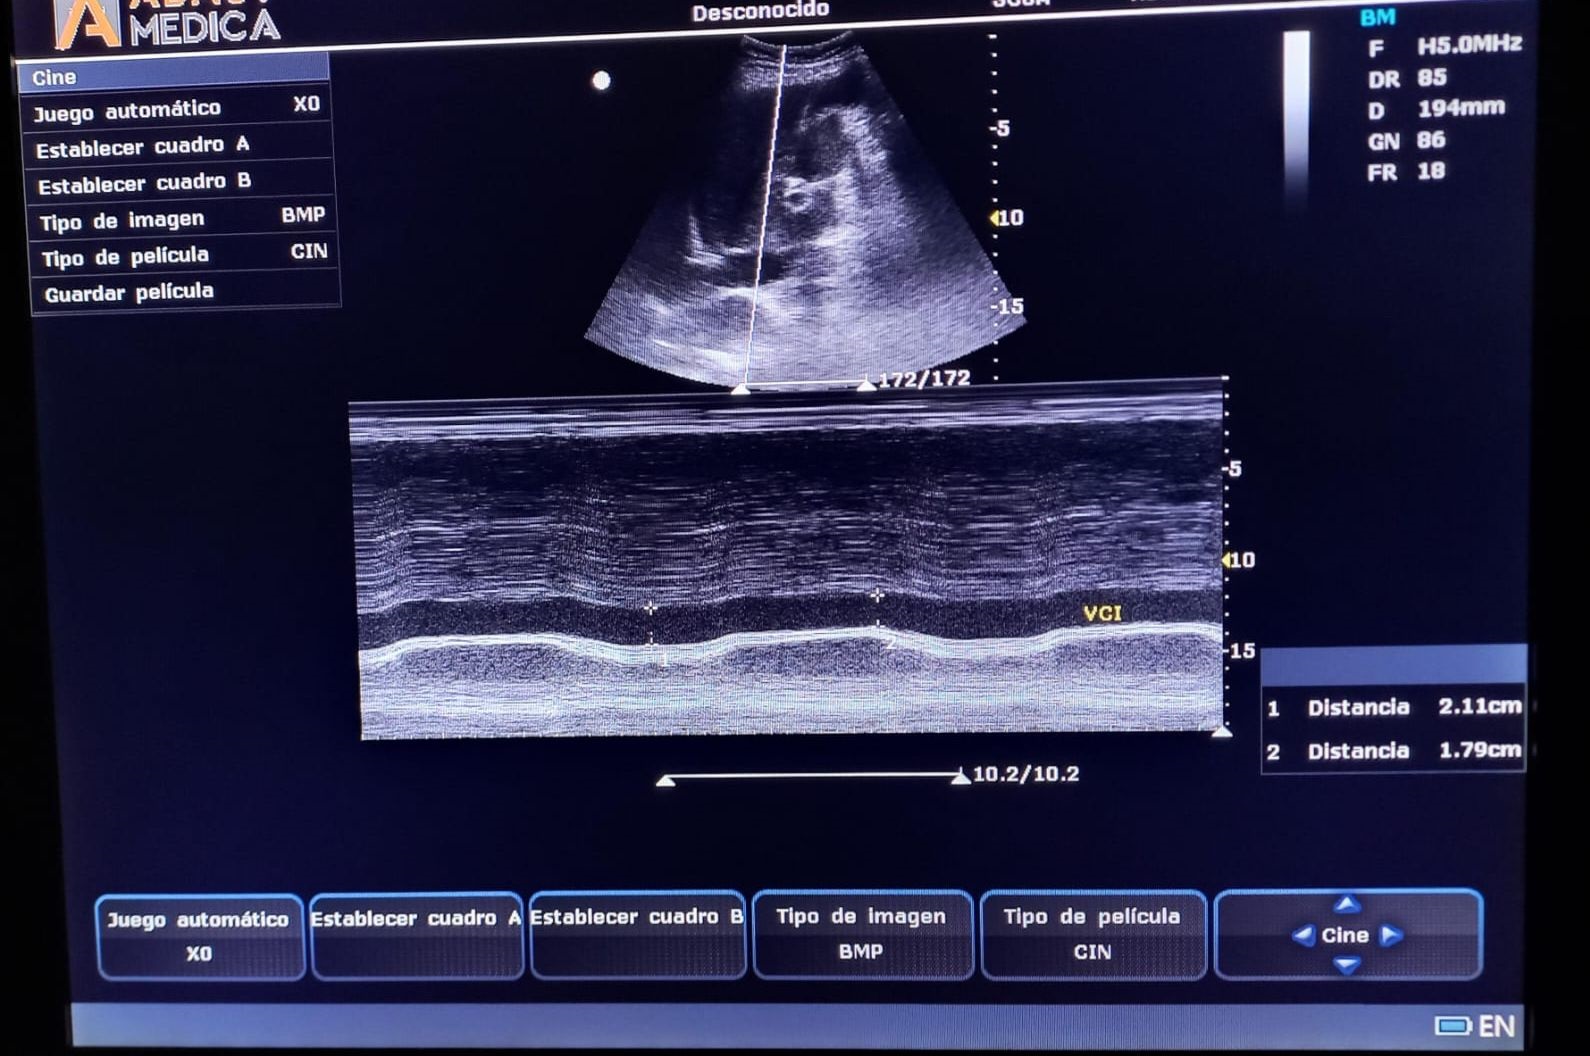

Desde 2022, tras la incorporación de un ecógrafo portátil en nuestro servicio, iniciamos formación específica en ecografía pulmonar, lo que permitió valorar el grado de congestión y la presencia de derrame pleural (DP) en pacientes con insuficiencia cardíaca congestiva (ICC), así como condensaciones pulmonares en casos de neumonía. En 2024, cursamos un Máster en ecografía clínica para atención primaria, incorporando el protocolo VEXUS para evaluar la congestión venosa sistémica. En 2025, completamos dos cursos semipresenciales que consolidaron esta práctica. La ecografía se integró en las visitas domiciliarias, optimizando tratamientos deplectivos y permitiendo seguimiento sin necesidad de traslados hospitalarios. El análisis de su uso entre enero de 2024 y junio de 2025 evidenció su valor clínico y la necesidad de formación específica para el equipo médico de HAD-AI.